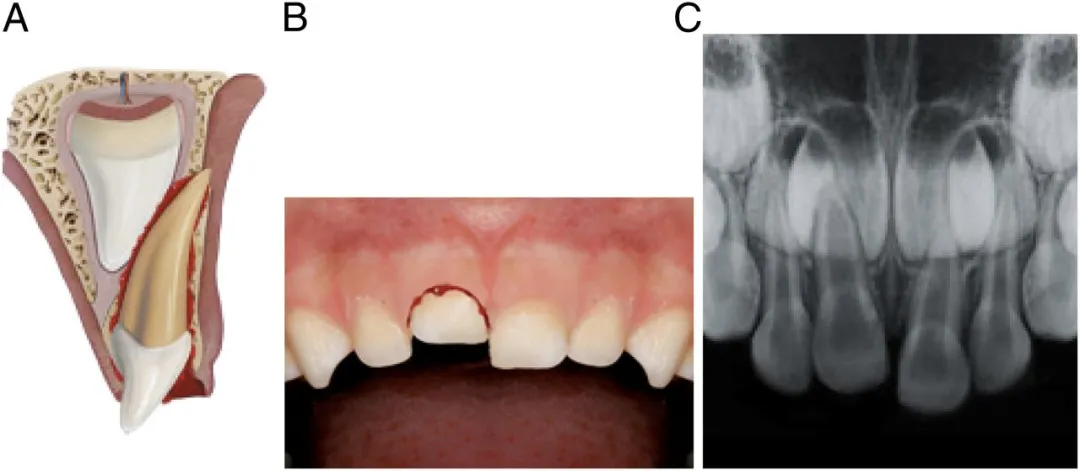

1、牙齿摔“歪”

摔歪的牙齿通常是牙齿尖往里(舌侧方向)歪。

严重的牙齿可能摔“短”一截,甚至摔没了,整颗牙直接“楔”进牙槽骨里。

摔歪的牙齿,一般伴有疼痛、松动、出血,同时出现咬合障碍,家长没有什么急救方法,能做的就是尽快就诊。

脱位幅度小的,医生可能会什么都不做,等牙齿自己复位;也可能手动把牙齿复位,然后等它自己长好;严重的,可能上夹板固定,跟处理骨折一样;再严重的,可能直接拔掉。